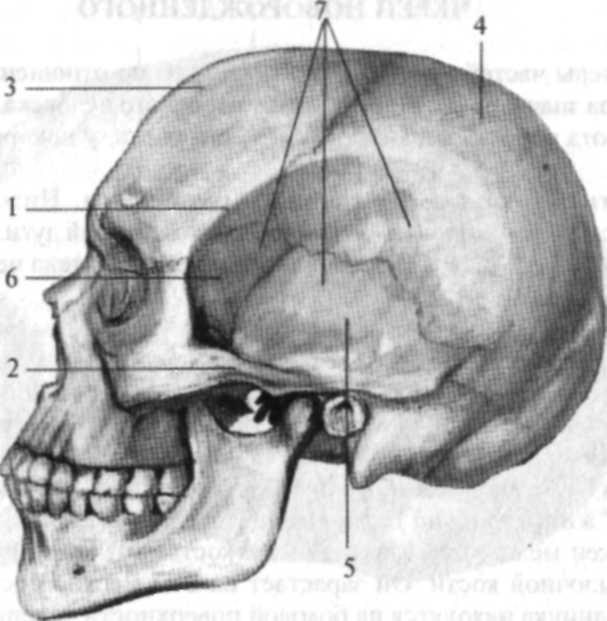

Анатомические особенности: фотографии ямок черепа, височной и подвисочной крылонебной